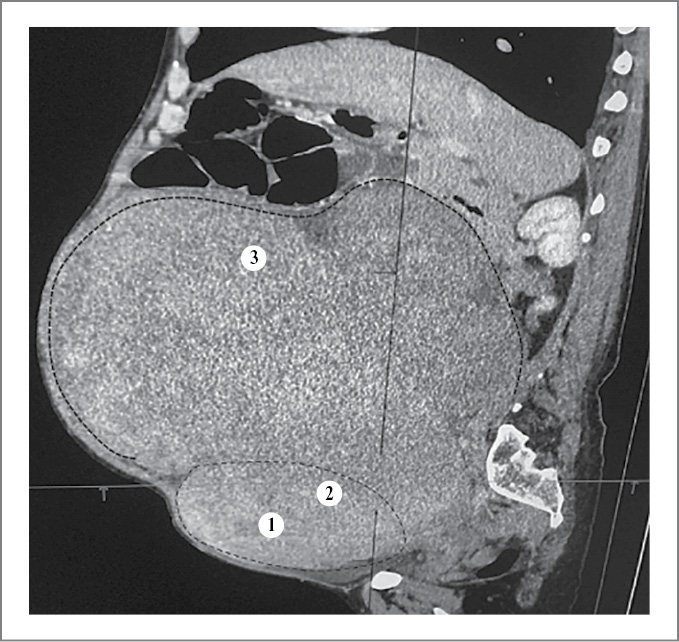

Проведенные трансабдоминальное и трансвагинальное ультразвуковые исследования оказались малоинформативными. Описано образование гигантских размеров миоматозной структуры, занимающее всю брюшную полость. Небольшое количество свободной жидкости (не исключается онкологическая патология яичников). Согласно данным компьютерной томографии органов брюшной полости и малого таза с внутривенным контрастным усилением выявлено объемное образование малого таза и брюшной полости значительных размеров. Дифференциально-диагностический ряд включал саркому, рак яичника с канцероматозом. Отмечены асцит, признаки дислокационного синдрома и тонкокишечной непроходимости (рис. 2).

Рис. 2. Компьютерная томография брюшной полости: 1 – полость матки; 2 – тело матки; 3 – миоматозные узлы.

Fig. 2. Abdominal computed tomography: 1 – uterine cavity; 2 – uterine body; 3 – fibroid nodes.